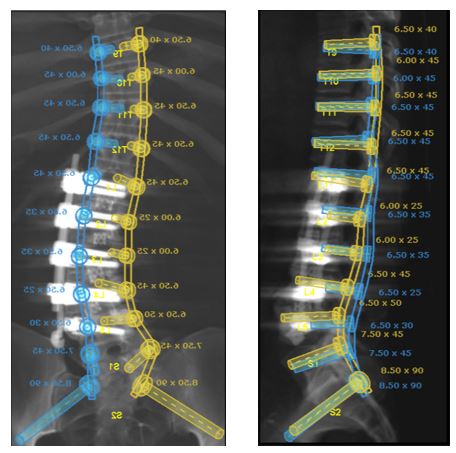

Update on the cervical epidural abscess case: Successful partial C4 corpectomy led to significant neurological recovery. Abscess was more phlegmon than liquid. Used fibular allograft for stability.

-Partial corpectomy offers excellent decompression + stability.